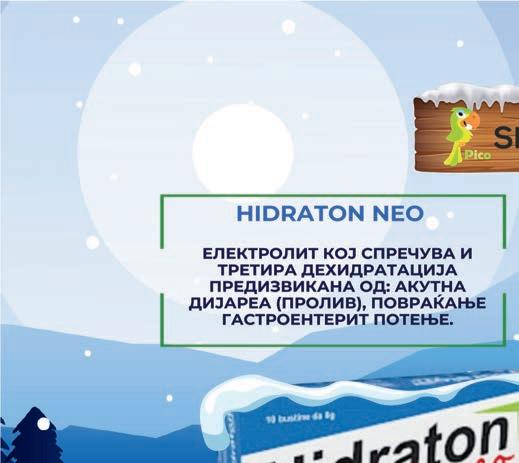

Прашок

Производ